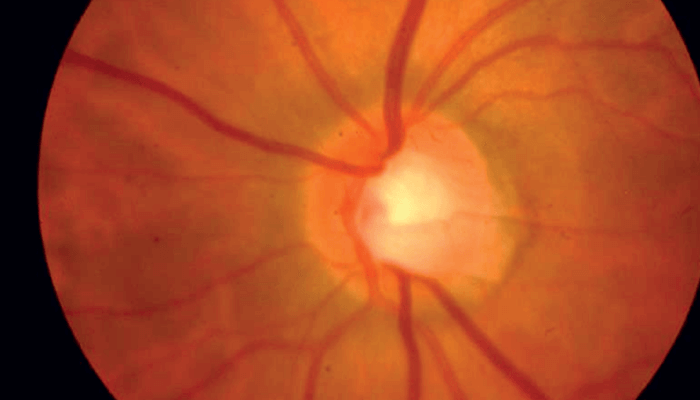

A 57-year-old Caucasian woman with a longstanding history of glaucoma and significant visual field loss in her right eye presented with treated intraocular pressures in the high teens. Her visual field in the right eye showed a deep superior paracentral defect close to fixation, and the left eye showed scattered defects but was grossly normal. Dilated fundus examination on the right eye revealed a cup to disc ratio (C/D) of 0.7 with an inferior notch, and on the left eye a C/D of 0.6 (see Figure 1).